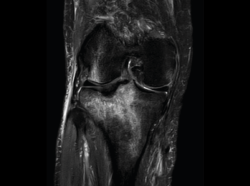

La RM es la técnica de elección en el diagnóstico de la patología meniscal(17)(Figuras 30, 31, 32, 33, 34 y 35).

Figura 32. Corte de secuencia coronal T2 Fat-Sat de resonancia magnética de rodilla: rotura de menisco interno horizontal.

Figura 33. Corte de secuencia sagital T2 Fat-Sat de resonancia magnética de rodilla: menisco interno con cambios mucoides.

Figura 34. Corte de secuencia sagital T2 Fat-Sat de resonancia magnética de rodilla: rotura en asa de cubo desplazada al asta anterior del menisco externo.

Figura 35. Corte de secuencia coronal y sagital de resonancia magnética de rodilla: rotura en asa de cubo del menisco interno con fragmento desplazado al intercóndilo.

1.2. Ligamentos